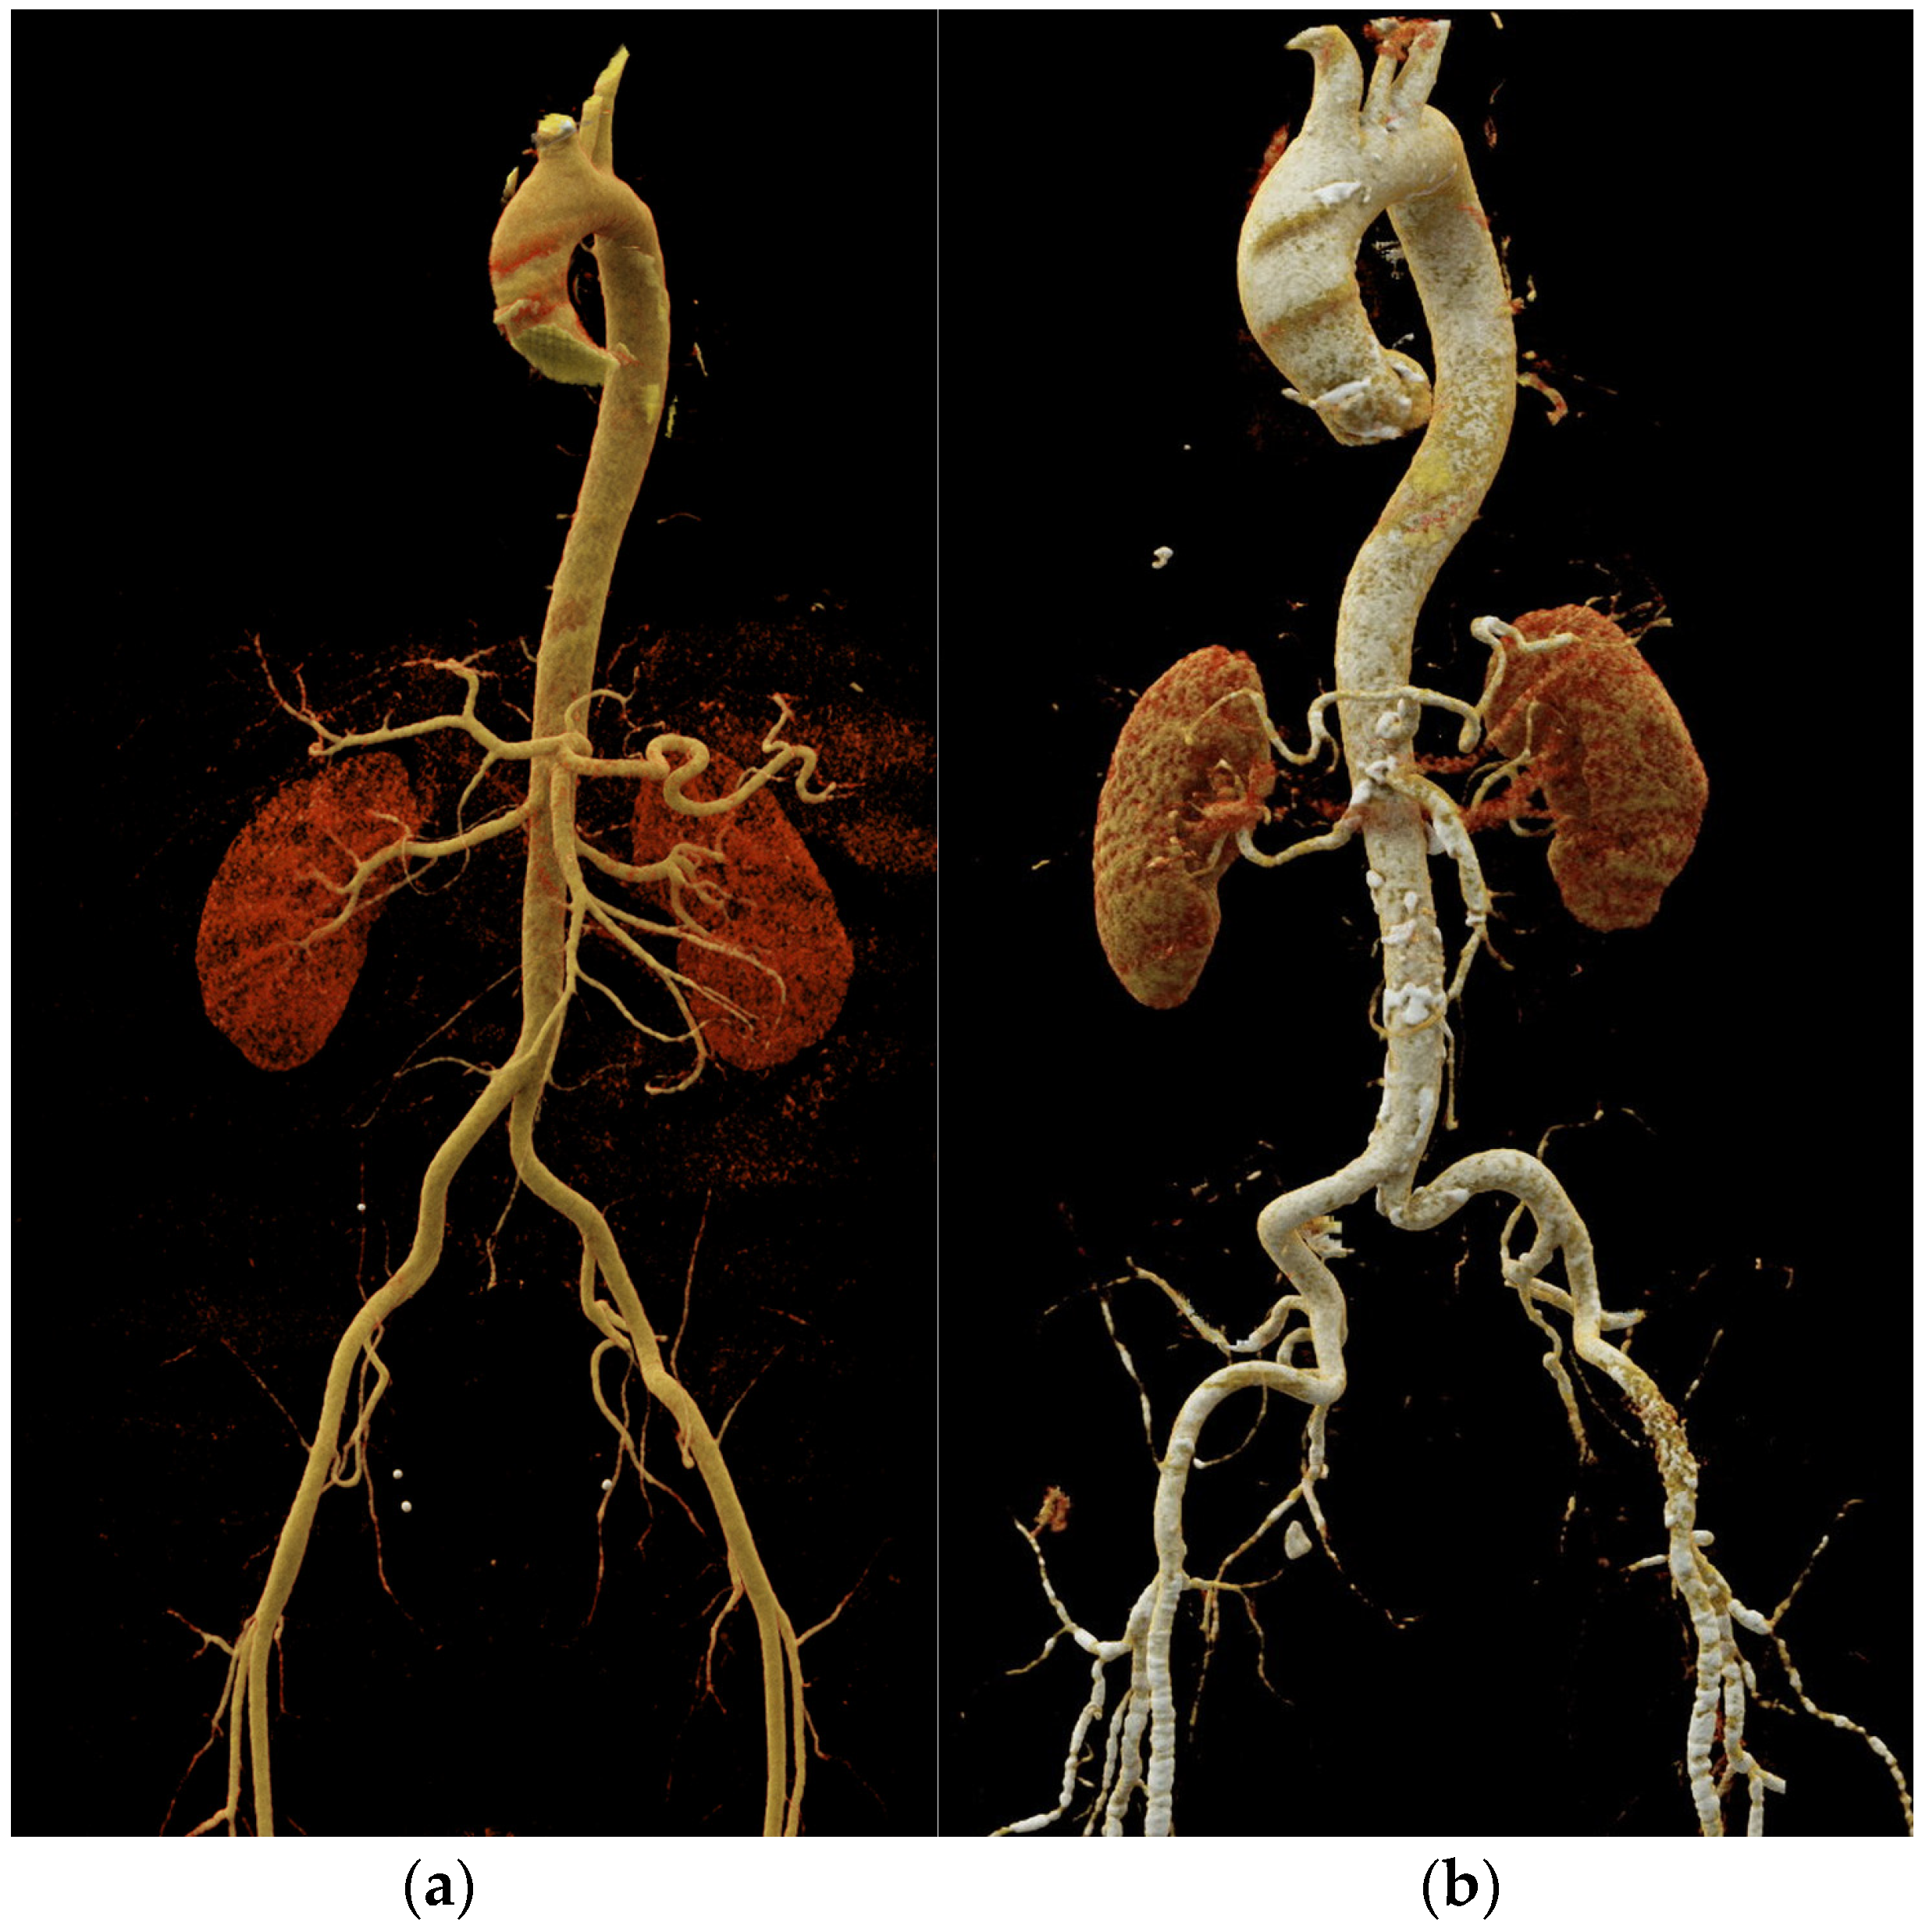

2. Vascular Aging

5.2. Computed Tomography

| Vascular aging | |

| Atherosclerosis | Non-calcified and calcified atherosclerotic plaques |

| Arterial dilatation and elongation | Arterial tortuosity, increased diameter and length |

| Computed tomography | Coronary artery calcium (CAC) scoring Coronary CT angiography (CCTA): coronary stenosis and plaque assessment Aortic morphology and stiffness (aortic strain and distensibility) | Improvements in risk classification around treatment decision thresholds (CAC scoring) First-line imaging modality in patients with suspicious chronic coronary syndrome (CCTA) First-line imaging modality for acute aortic syndrome, commonly used for follow-up of aortic diseases (especially in older individuals) | Fast performance Detailed depiction of coronary anatomy (plaque morphology, luminal stenosis) and valvular morphology Method of choice for planning aortic interventional or surgical procedures | Ionizing radiation Use of iodine contrast agents High costs Imaging artifacts (motion artifacts, blooming artifacts) Limited functional information |